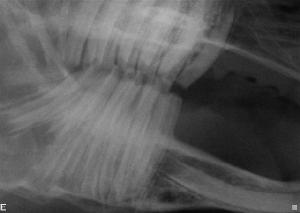

The lower

cheek teeth apices diverge and protrude toward the ventral-lingual aspect of

the mandible. The upper cheek teeth

converge and project toward the buccal aspect of the maxilla.